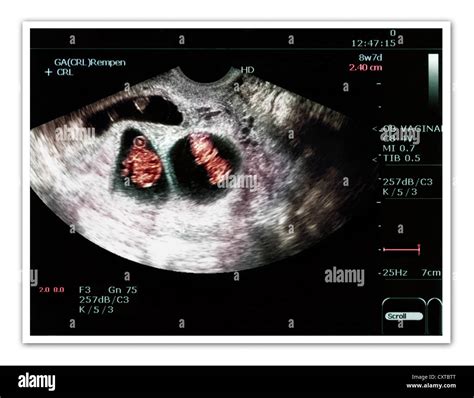

15 Week Sonogram

Pregnancy is an exciting journey filled with milestones, and one of the most anticipated moments is the 15 week sonogram. This ultrasound scan provides valuable insights into the development of the fetus and offers parents a glimpse into their baby's world. Understanding what to expect during a 15 week sonogram can help alleviate anxiety and enhance the overall experience.

A 15 week sonogram is an ultrasound examination performed around the 15th week of pregnancy. It is typically part of the second-trimester ultrasound, which is often scheduled between 18 and 22 weeks. However, some healthcare providers may perform an earlier scan to check on the baby’s development and ensure everything is progressing smoothly.